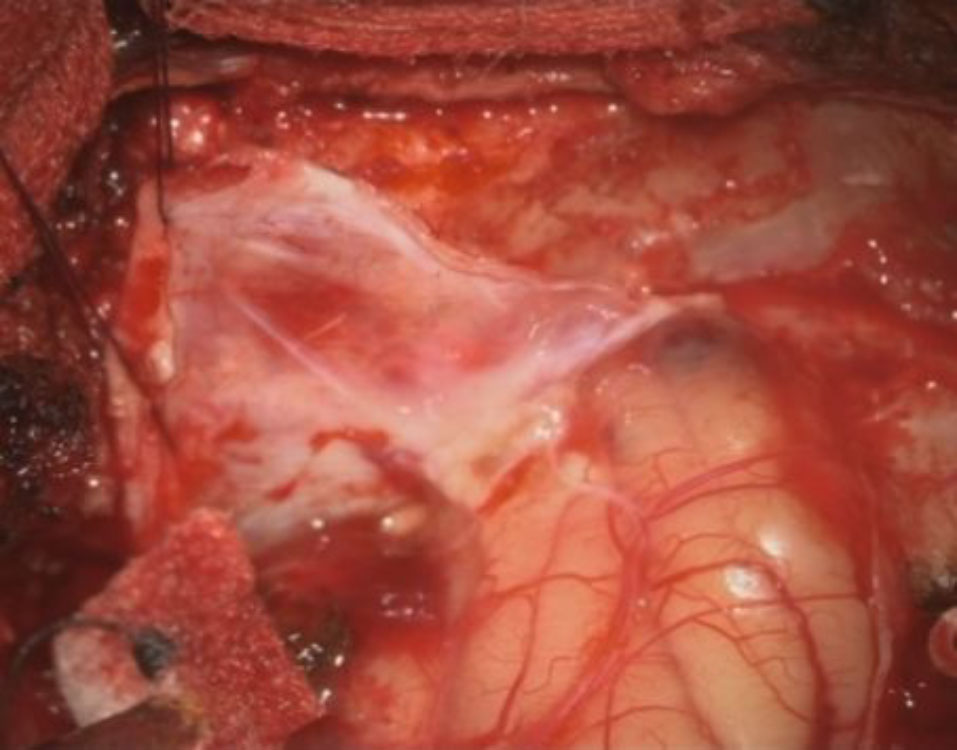

症例 '25年12月

No.

709

年_番号

手術年月

患者年齢

’25_111

'25年12月

60代

病名

術式

備考

左頭蓋窩腫瘤

頭蓋内腫瘍摘出術

断層撮影

術中写真

摘出 前

摘出 中

摘出 後